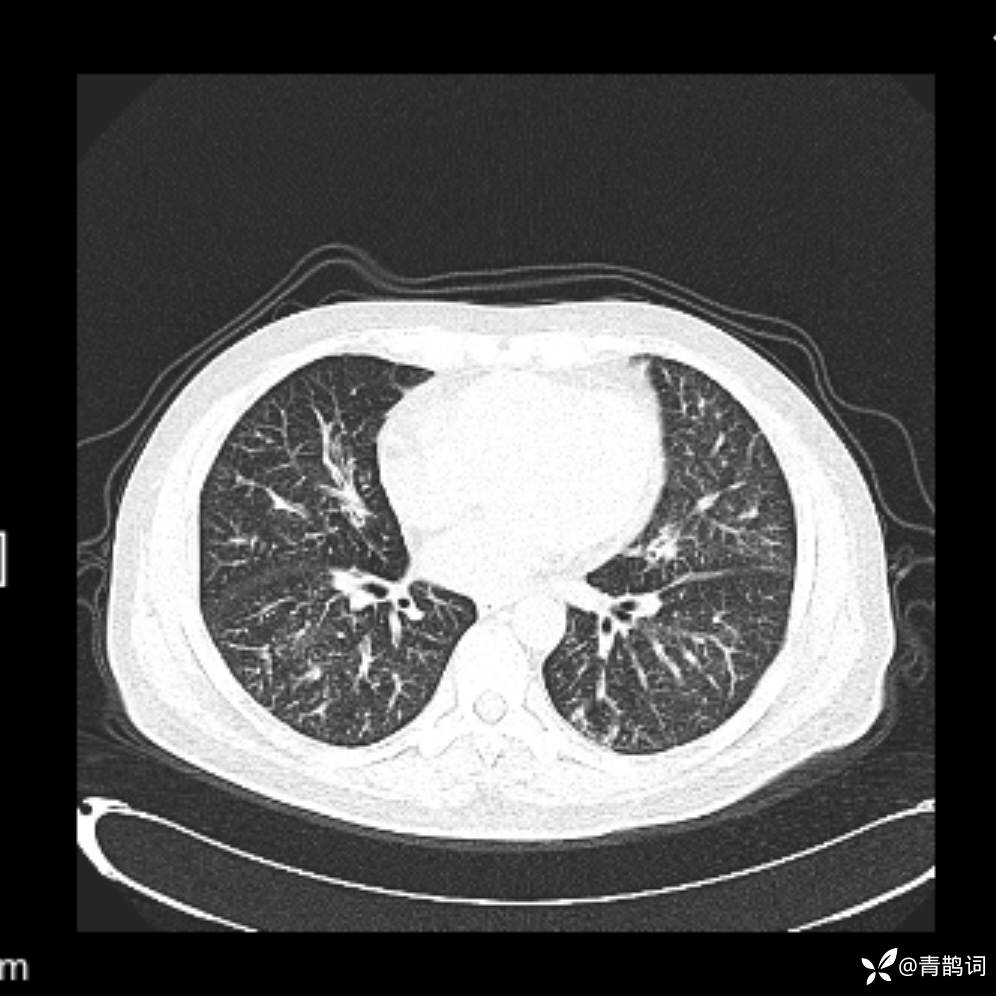

患者年龄:30岁。

患者性别:男。

简要病史:左颜面部肿胀2年,反复咳嗽咳痰,逐渐加重。

结合病史及影像学表现,期待评论区各位老师各抒己见~